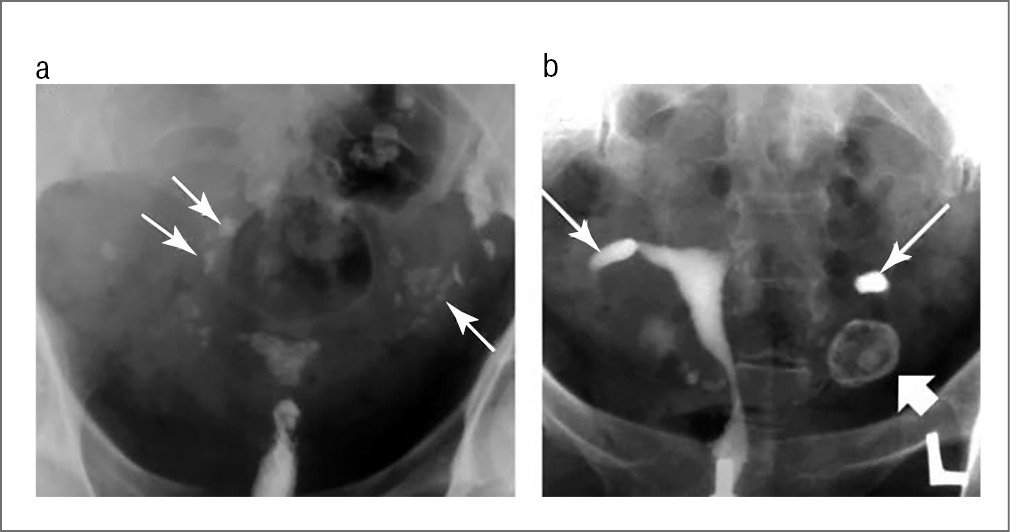

Туберкулез следует заподозрить при наличии синехий, трубной непроходимости в переходной зоне между перешейком и ампулой, множественных сужений, обызвествленных лимфатических узлов, неравномерных линейных или узелковых обызвествлений в области придатков (рис. 1, a, b).

Рис. 1. a. Множественные обызвествленные лимфатические узлы у больной ТЖПО. Обызвествленные лимфатические узлы в области малого таза (длинные тонкие стрелки) и по ходу фаллопиевых труб. Неравномерный контур матки, ее емкость снижена. b. Cлева видна большая тень кальцинированного яичника. Гидросальпинкс дистальной части обеих труб. Источник: F. Ahmadi и соавт. [54]. / Fig. 1. a. Multiple calcified lymph nodes in a patient with female genital tuberculosis (FGT). Calcified lymph nodes in the pelvic area (long thin arrows) and along the fallopian tubes. Irregular uterine contour; the volume of the uterine cavity is reduced. b. A large shadow of a calcified ovary can be seen on the left. Hydrosalpinx of both tubes' distal parts is observed. Source: F. Ahmadi et al. [54].